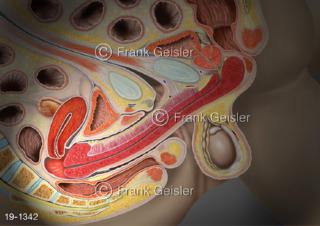

Bilder zu Medical Art und Anatomie-Art, visuelle Darstellung medizinischer Inhalte künstlerisch umgesetzt, medizinisches Fachwissen als künstlerische Gestaltung für die Ausbildung, zur Patientenaufklärung und zur wissenschaftlichen Kommunikation, als künstlerische Dekoration in Gesundheitseinrichtungen und Arztpraxen

© MediDesign Frank Geisler